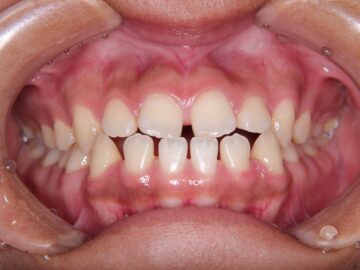

ご相談時

前歯にすき間がある。

上下顎全体にブラケットを装着し、隙間を閉じることを勧めた。